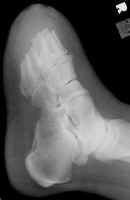

The images above demonstrate a transmetatarsal amputation through all five digits.

The bone edges are beveled and there is a generous soft tissue pad.